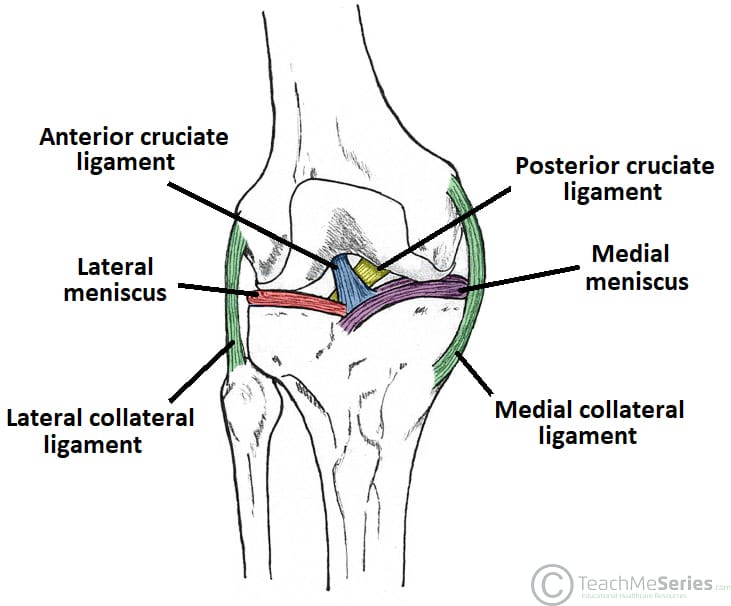

The ACL is an important stabiliser of the knee joint, being the primary restraint to limit anterior translation of the tibia (relative to the femur) and also contributing to knee rotational stability (particularly internal). Consequently, a tear of this important ligament often results in significant functional impairment of the joint.

Differential diagnoses for an anterior cruciate ligament injury include a tibial plateau fracture or distal femur fracture, a meniscal tear, collateral ligament injury, or a quadriceps tendon injury

*50% of ACL tears will also have a meniscal tear, with the medial meniscus the more commonly affected